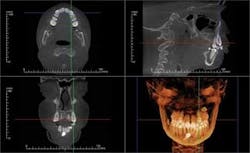

All CBCT manufacturers include OEM (Original Equipment Manufacturer) software with their machines. This software varies with the specific units, but generally includes a method of viewing the scan in an interactive frontal, sagittal, and coronal mode known as Multi-Planer Reconstruction (MPR). Each scan is reviewed first by browsing through the cross sections in all three planes and noting any findings, with particular attention paid to the diagnostic condition of interest (Figure 1).

Specialized orthogonal cross sections, such as panoramic planings, are performed to elicit a more directed view of areas of interest. The Hounsfield density measures the relative density of the involved structures and offers insight into the nature of the lesion. Most OEM software includes a 3-D viewer which can be applied to the scan to observe the volume of the target and its juxtaposition to other structures. Measuring tools in the software enable precise measurements in both the 2-D and 3-D images. The 3-D images can be cropped to decrease superimposition of adjacent structures — surface rendered to view skin and airway volume — all of which can be rotated for viewing at any angles. Most OEM packages have a function which displays corrected tomographic AP and coronal slices through the temporomandibular joints.